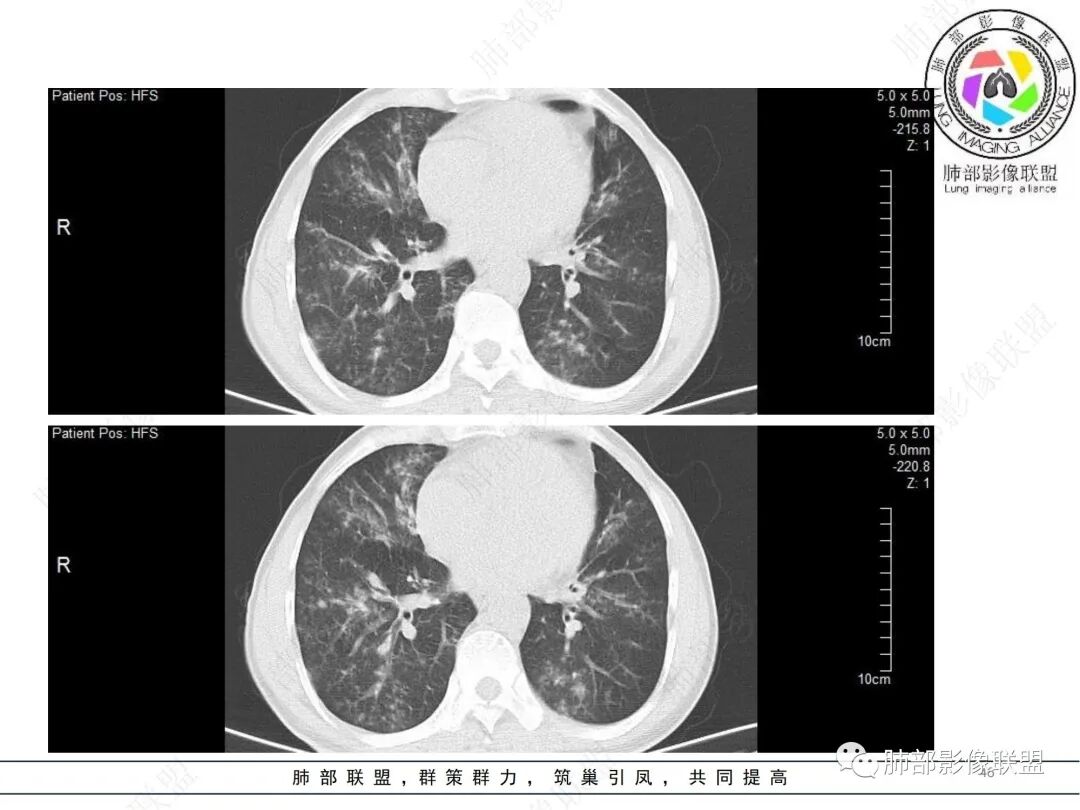

58岁男性,咳嗽胸闷3天,咳较多褐粘液痰,无发热。有2型糖尿病病史。白细胞与中性粒细胞升高。CRP升高。鳞状上皮细胞癌抗原轻度升高。结核T细胞免疫斑点实性阳性。肺炎支原体、衣原体IgG轻度升高。支气管镜显示支气管炎性改变、右肺下叶背段管腔狭窄。2.影像特点:

2022.6.24CT显示两肺弥漫性段、亚段支气管壁增厚(两肺各叶都累及),增厚的支气管壁外可见沿着支气管分布的渗出、实变影。另外远端肺内亦可见多发树芽影、结节影,其边界欠清晰。右肺下叶基底段局部胸膜下亦可见小斑片影,边界不清。2022.6.27CT显示两肺增厚的支气管壁外的渗出实变影明显增多、范围更广。远端肺内病灶亦增多、范围增大。部分位于胸膜下的病灶可见侧向融合趋势。3.病例分析:

影像学病灶双肺分布,支气管广泛增厚,较少见于普通社区肺炎,而更多见于气道侵袭性曲霉病。病原学检查证实烟曲霉感染的存在。

本案之未解之处在于三天内的进展太快,实验室炎性指标太高,合并细菌感染的可能性仍有待排除。